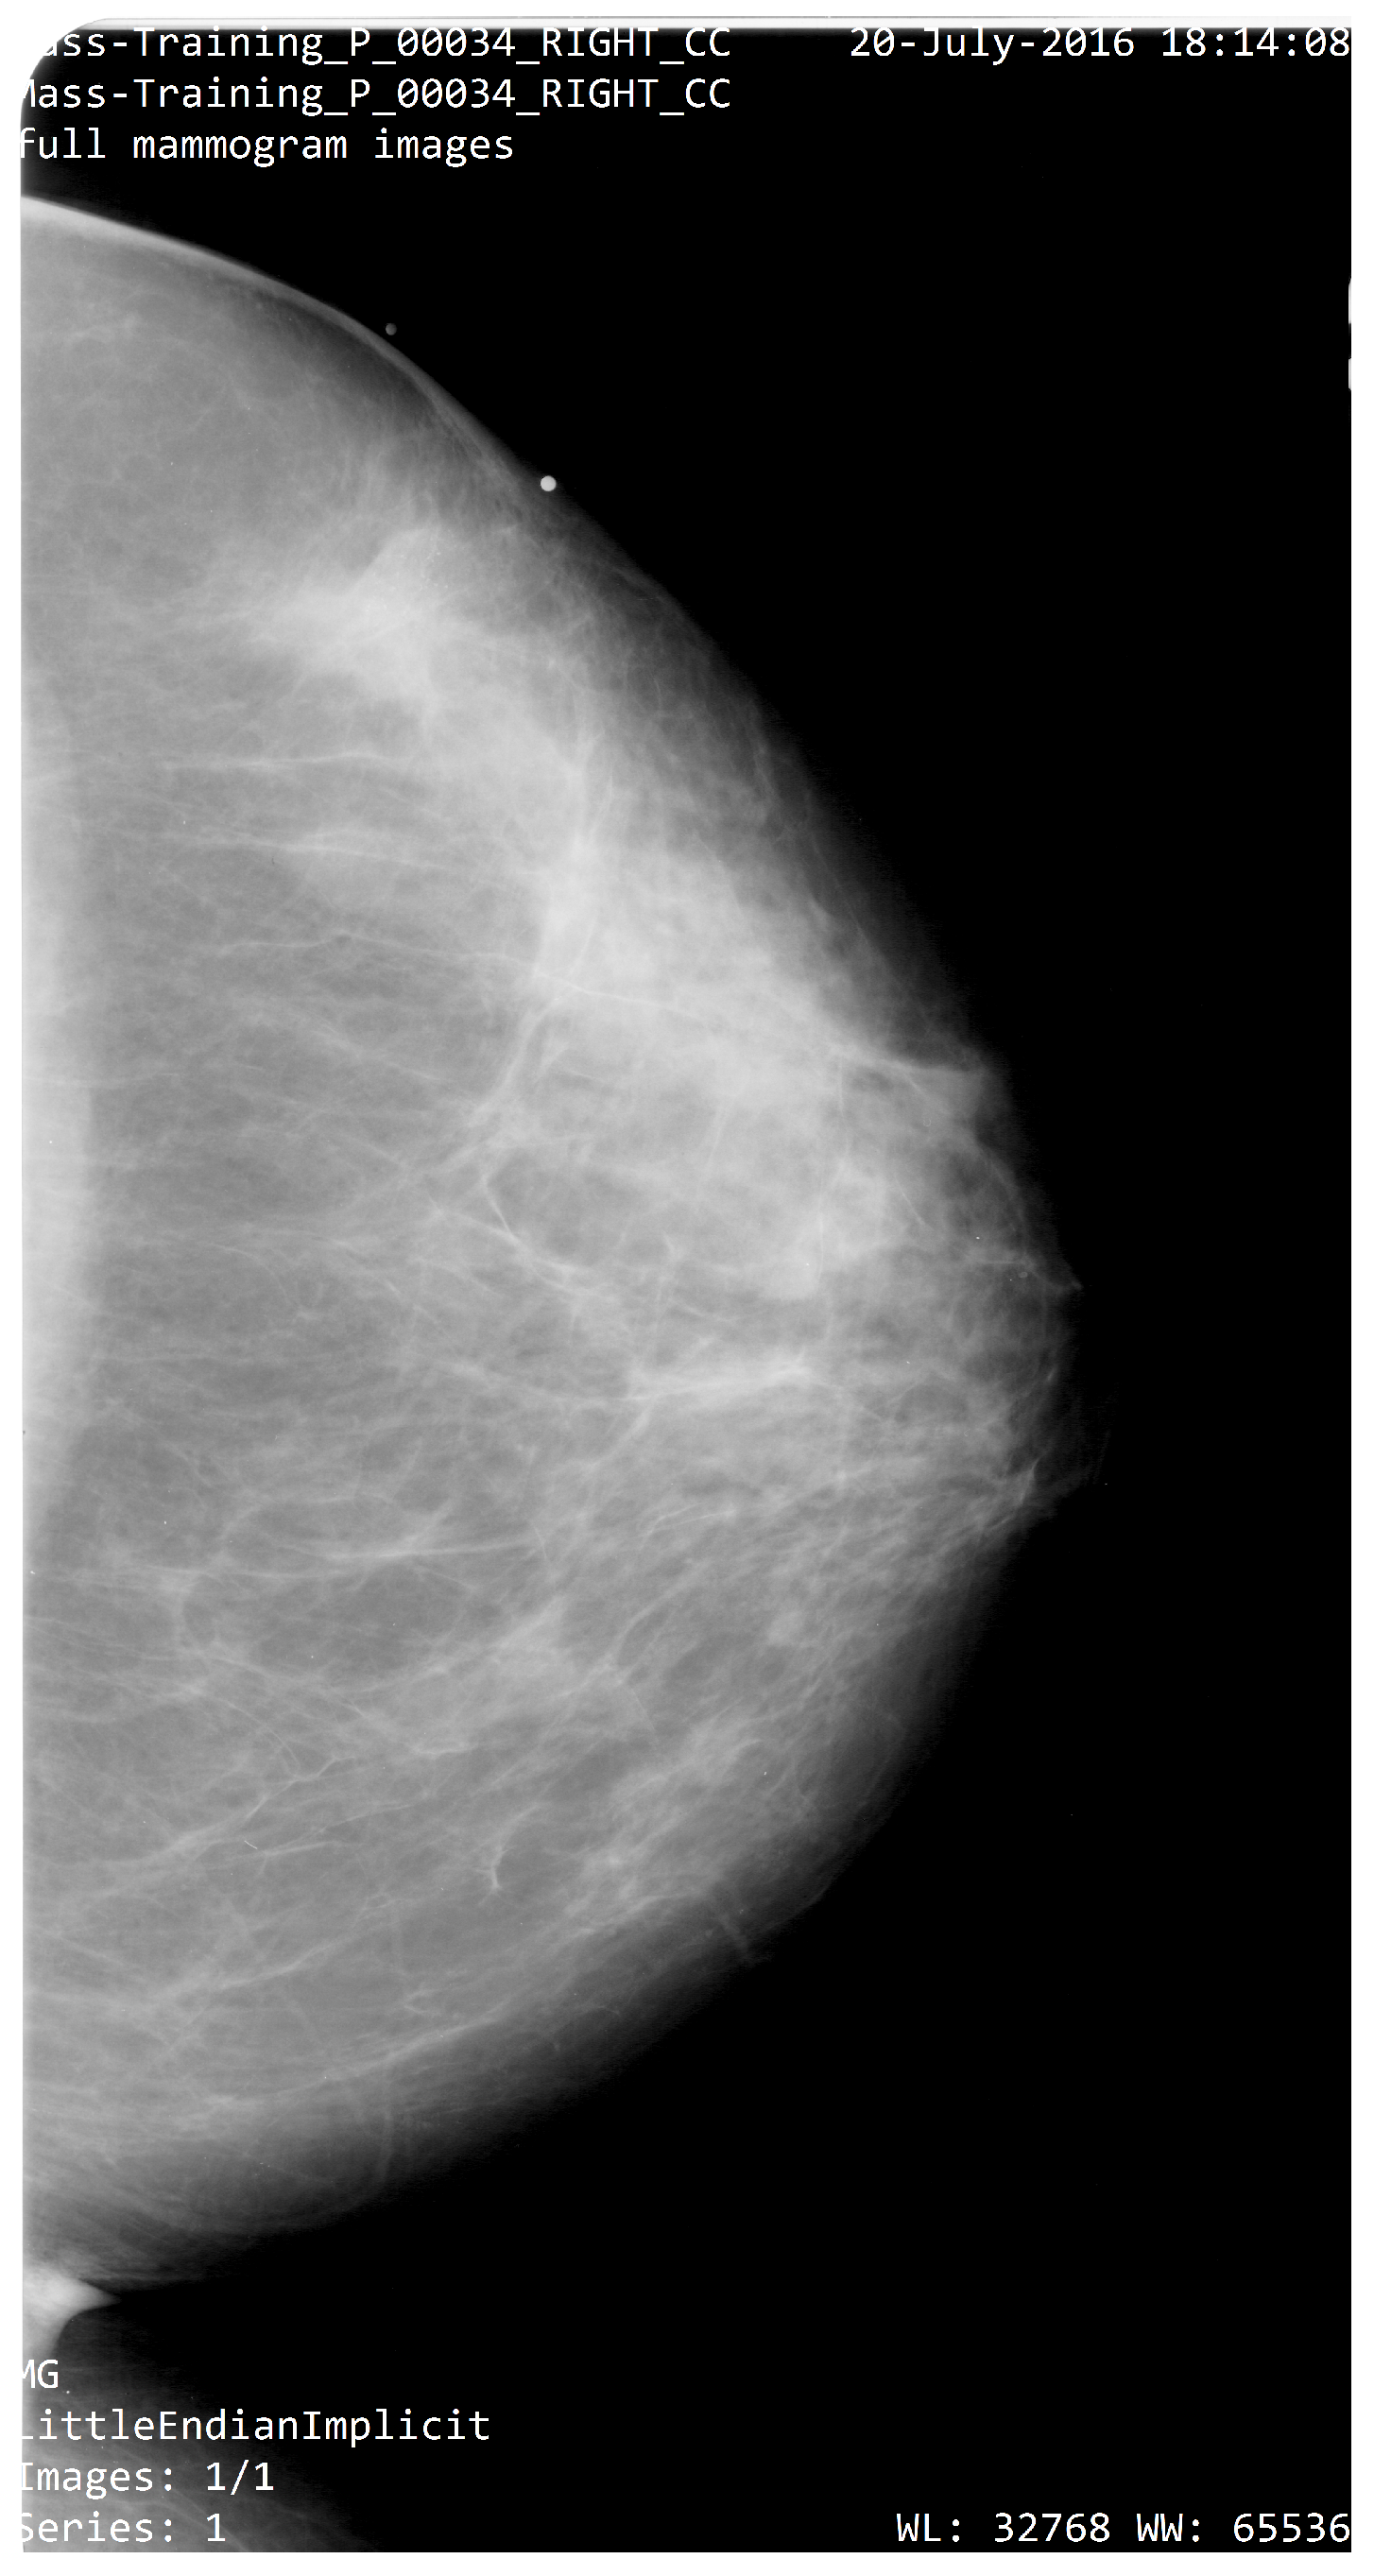

2.1.1. Data Description

The Digital Data base for Screening Mammography (DDSM) is a data base collection of 2620 study cases at the University of South Florida [39]. This data set includes two images of each breast, patient information and an image information system. Recently, another data base was extracted and standardized to test scientific methodologies, and evaluate their performance [40]. This CBIS-DDSM (Curated Breast Imaging Subset of DDSM) is a data subset of the original DDSM database. The digital mammography was decompressed and converted to a Digital Imaging and Communications in Medicine (DICOM) format (as shown in Figure 2). The data set imaging contains the left and right of the craniocaudal view (CC) and medial lateral oblique view (MLO) of the breast images for each patient. The data set also includes descriptions of the location of the breast lesion on calcifications and masses, bounding boxes, and pathology diagnosis for training test images. In order to complete the first stage, it is also necessary to provide a region-of-interest (ROI) segmentation on the breast lesion. Abnormalities were cropped by determining the bounding rectangle of the abnormality with respect to its ROI. The data set contains 753 calcification cases and 891 mass cases. There are Breast Imaging Reporting and Data System (BI-RADS) descriptors for mass shape, mass margin, calcification type, calcification distribution, and breast density. Table 1 shows some characteristics of the CBI-DDSM.

Figure 2. Original mammogram (CC) obtained from CBIS-DDSM data-sets.